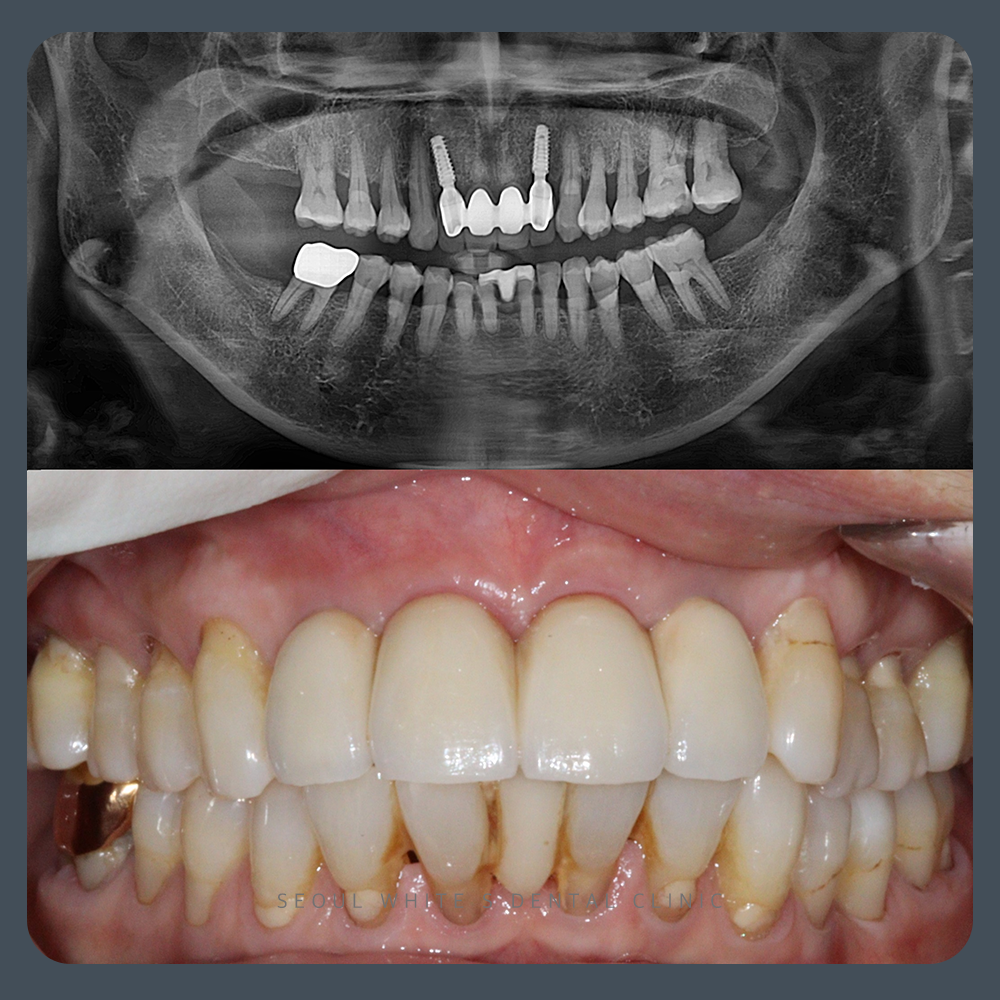

술후 사진

24.02.28

이전에는 환자분이 기존 브릿지 때문에 크게 웃을 수 없을 정도로 많은 걱정을 하셨습니다. 하지만 이제 환자분은 자연스러운 임플란트 브릿지에 완벽하게 적응하셔서 자신 있게 웃을 수 있게 되었습니다.

브릿지 임플란트는 그 어떤 부위보다도 뛰어난 심미성이 요구됩니다. 그러나 심미성뿐만 아니라, 오랜 시간 동안 안정적인 임플란트를 유지하려면 철저한 골이식이 필수적입니다. 파노라마 사진을 통해 보실 수 있듯, 기존 브릿지 아래쪽의 골 상태와는 달리 훨씬 건강하고 좋은 골 상태를 확인할 수 있습니다.

골이식은 종종 원하는 대로 진행되지 않을 수 있지만, 영도치과 서울화이트S치과의 의료진은 다양한 골이식 사례를 경험한 의료진으로 구성되어 있어, 기능과 미적 효과를 동시에 만족시키는 골이식을 진행할 수 있습니다.